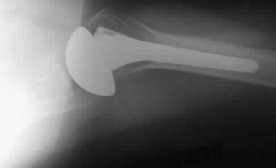

Question 46

A 65-year-old female with severe rheumatoid arthritis undergoes a linked (semi-constrained) total elbow arthroplasty (TEA).

Three years later, she develops rapid early polyethylene wear and aseptic loosening of the components. What is the most common iatrogenic cause of early bushing wear and failure in a linked TEA?

Explanation

In a linked or semi-constrained total elbow arthroplasty, the prosthesis acts as a hinge that allows some varus/valgus toggle. If the humeral component is placed with its axis of rotation malaligned compared to the natural anatomic axis of the elbow, it creates a kinematic mismatch. This generates excessive stress on the polyethylene bushings during flexion and extension, leading to accelerated wear, osteolysis, and early aseptic loosening.